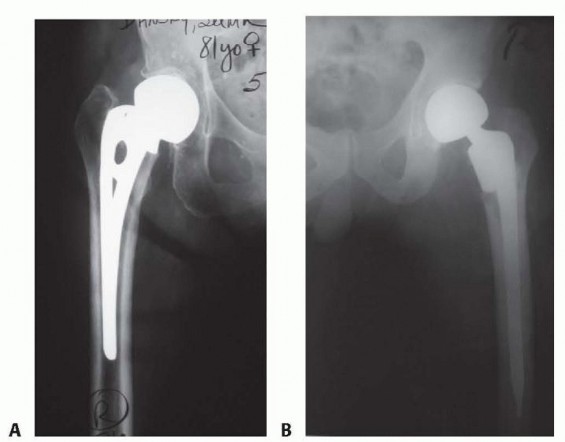

DEFINITION Femoral neck fractures are classified according to the Garden classification ( Table 1 ). 9 This c…